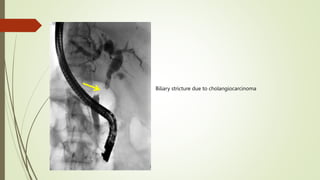

Biliary stricture due to cholangiocarcinoma

Biliary stricture dueto cholangiocarcinoma